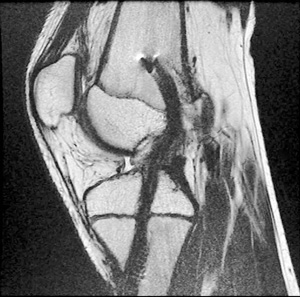

- Recomendamos la reconstrucción Transfisiaria con fijación alejada de la fisis, usando autoinjerto de semitendinoso y gracilis. Usamos un túnel central de 7 mm, relleno completo de los túneles y fijación alejada de la fisis (Fig. 5).

Figura 5: Corte sagital de control con resonancia magnética de paciente con reconstrucción de LCA con técnica transfisiaria. Se utilizó Transfix® y tornillo bioabsorbible que respeta la fisis.